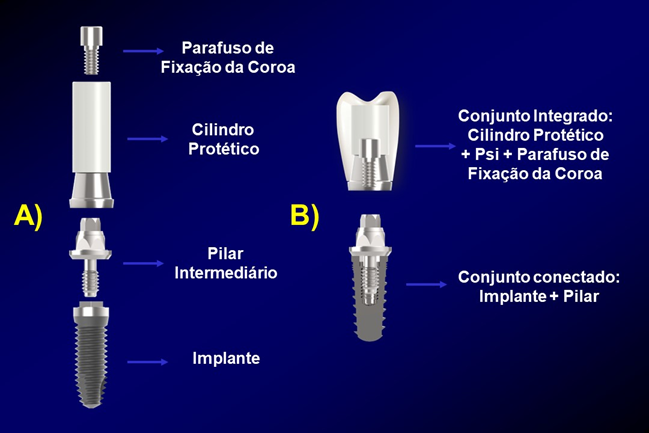

A finalização dos casos de prótese sobre implantes passa necessariamente pela escolha de um pilar intermediário entre o implante e a prótese (coroa). Em muitas vezes, o profissional fica em dúvida sobre como proceder em relação à sua escolha, indicações e técnicas de uso quanto ao passo a passo desses componentes. Assim, este artigo visa dar subsídios aos profissionais quanto à essa seleção e destacar a versatilidade do componente UCLA da Implacil De Bortoli.

Conceitualmente falando, temos que pilares intermediários são os componentes utilizados para fazer a ligação entre o implante e a prótese/coroa, representando de forma análoga o núcleo de uma prótese fixa convencional.

Outro fato que merece ser destacado é a forma de confecção das próteses sobre implantes, se direto na cabeça do implante ou se usando um pilar intermediário e parafusando ou cimentando a PSI sobre o pilar. Dessa forma, a primeira diferença entre o pilar UCLA e os demais pilares se refere à forma de confecção da PSI, uma direto sobre a cabeça do implante utilizando-se do pilar UCLA (assemelhando-se a um “pivot” cuja coroa está integrada ao núcleo-pino em um único sistema pela ausência de espaço interoclusal), e a outra forma em que o profissional fará uso do pilar e sobre este teremos uma prótese que será cimentada ou parafusada, vide imagens da Figura 2 (Zavanelli et al., 2003; Zavanelli et al., 2011).